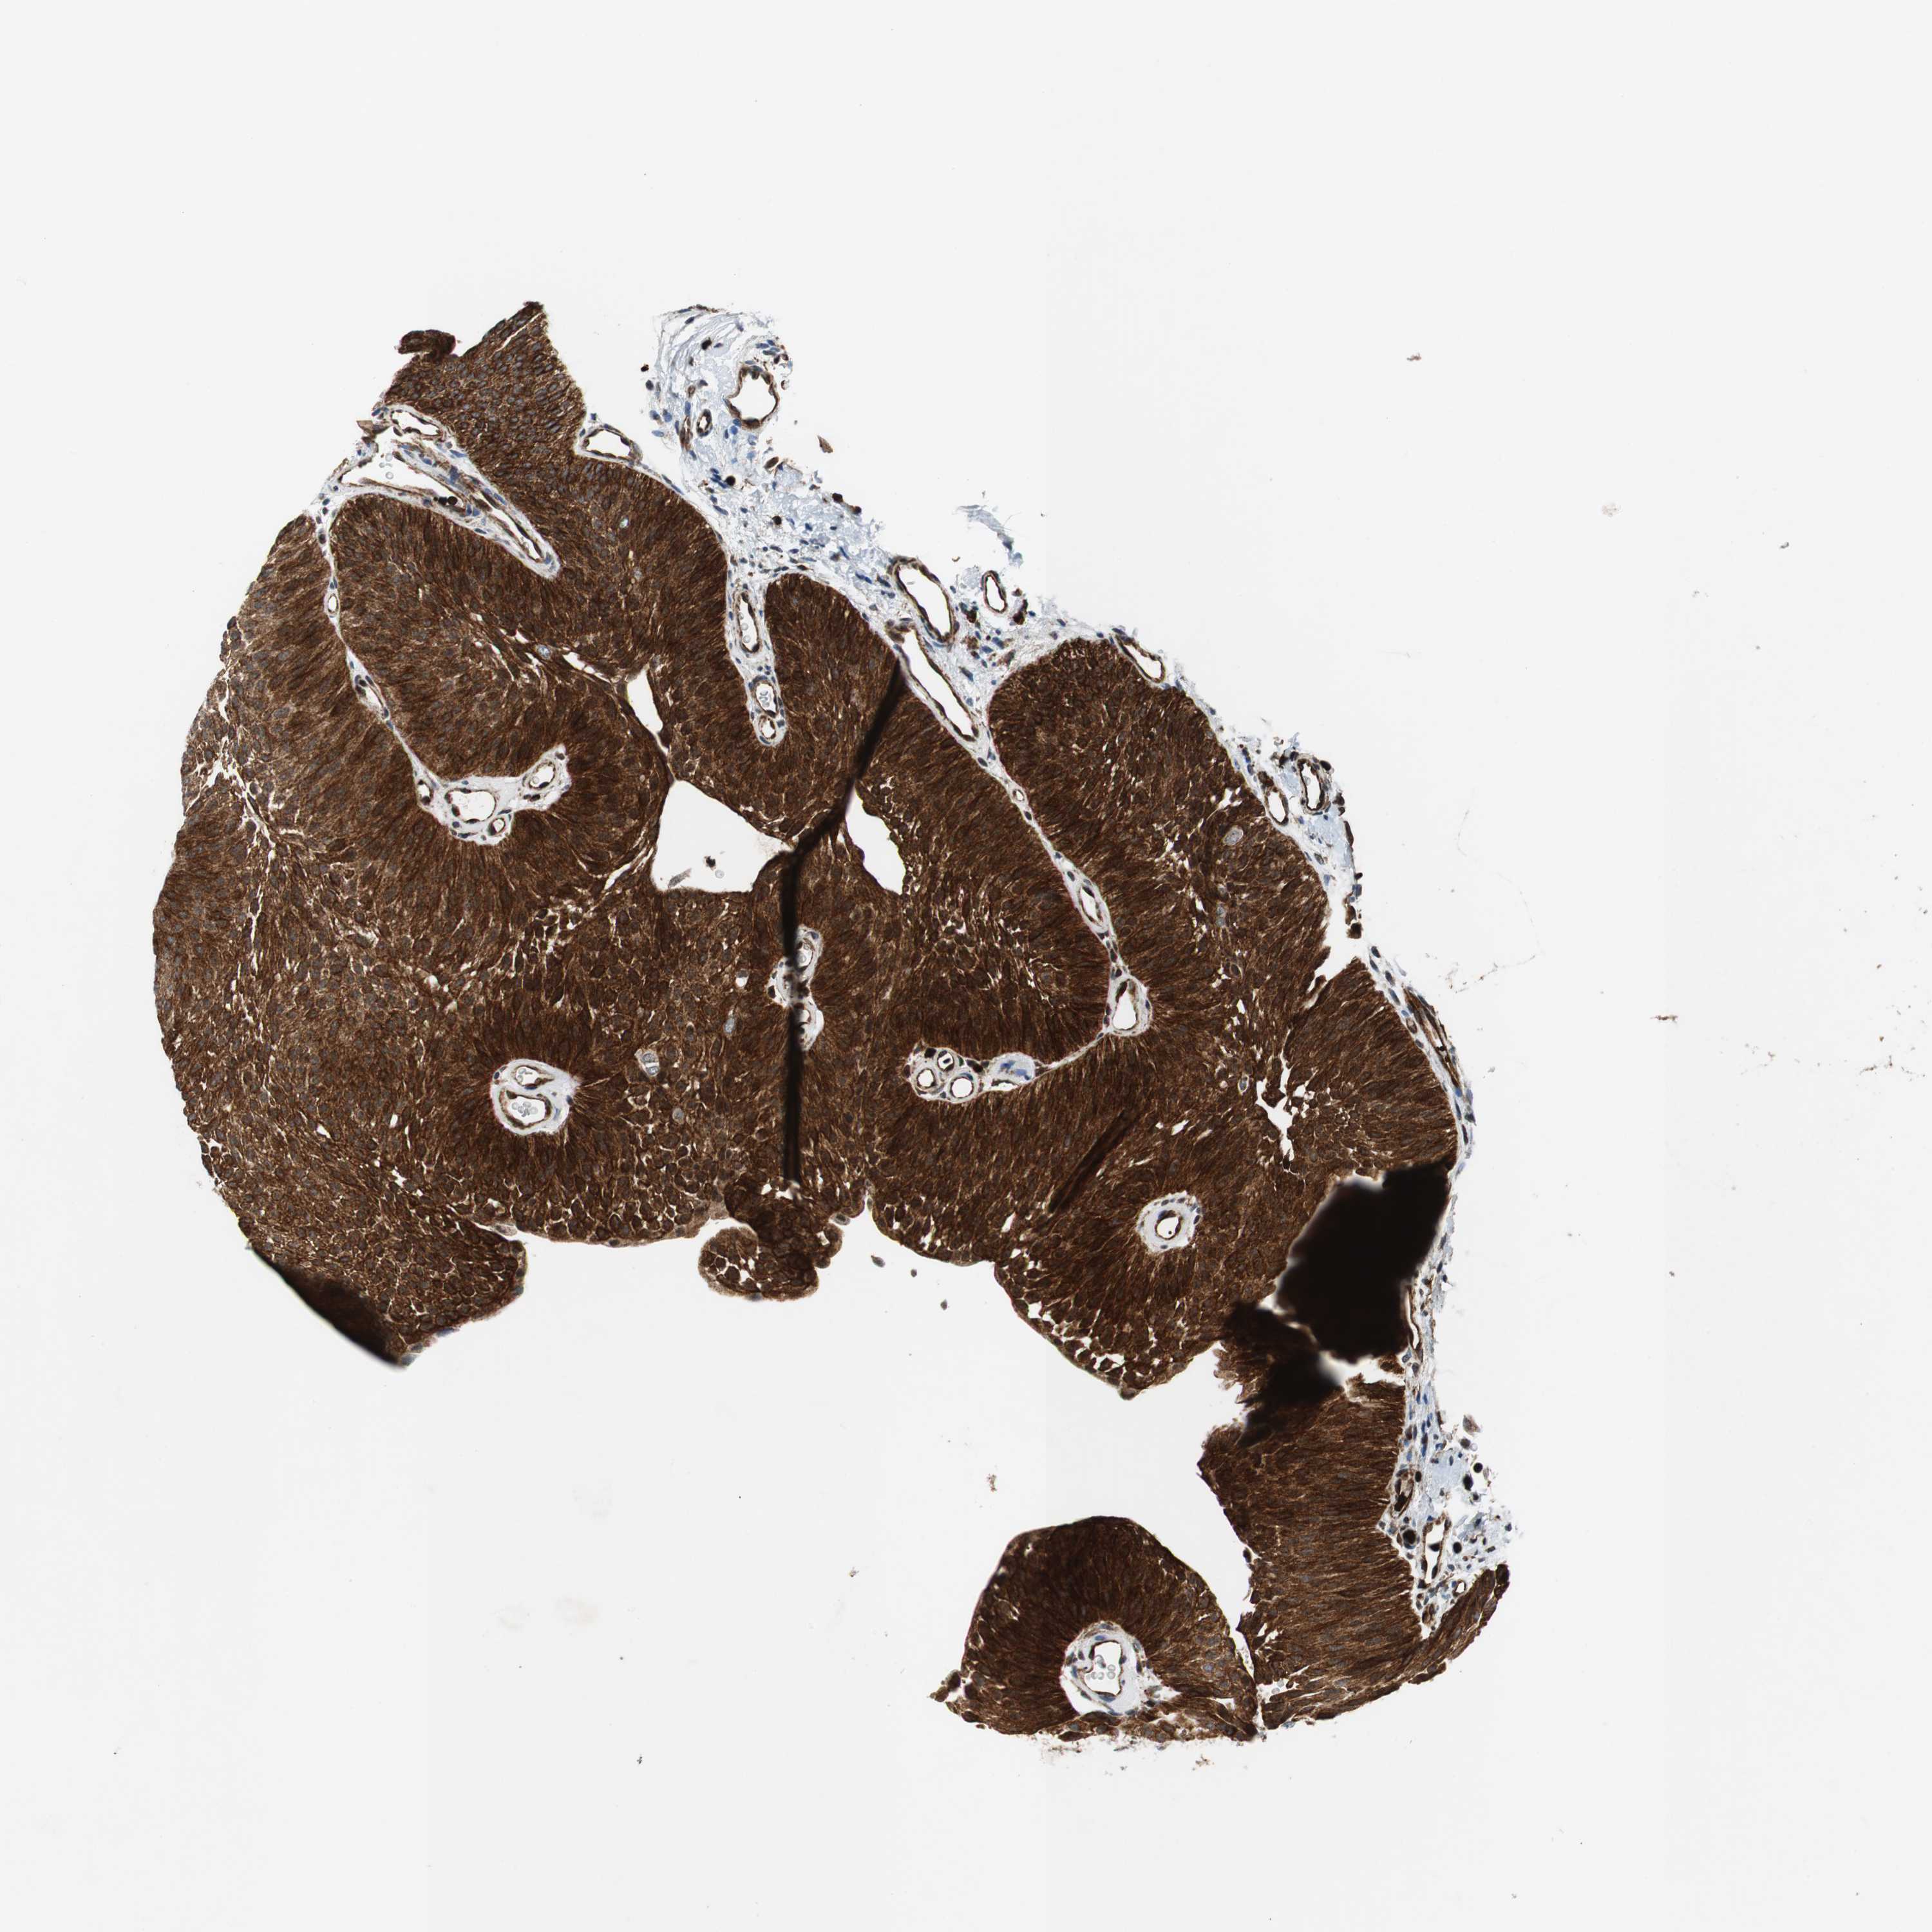

UROTHELIAL CANCER - Protein expressioni

A mouse-over function shows sample information and annotation data. Click on an image to view it in a full screen mode. Samples can be filtered based on level of antibody staining by selecting one or several of the following categories: high, medium, low and not detected. The assay and annotation is described here.

Note that samples used for immunohistochemistry by the Human Protein Atlas do not correspond to samples in the TCGA dataset.

Antibody stainingi

Antibody staining in the annotated cell types in the current human tissue is reported as not detected, low, medium, or high, based on conventional immunohistochemistry profiling in selected tissues. This score is based on the combination of the staining intensity and fraction of stained cells.

Each image is clickable and will lead to virtual microscopy that enables deeper exploration of all samples and also displays staining intensity scores, fraction scores and subcellular localization as well as patient and tissue information for each sample.

HPA039247

HPA043684

HPA063394

CAB004621

CAB005887

Staining

High

Medium

Low

Not detected

Intensity

Strong

Moderate

Weak

Negative

Quantity

>75%

75%-25%

<25%

None

Location

Nuclear

Cytoplasmic/membranous

Cytoplasmic/membranous,nuclear

Urothelial carcinoma, High grade

Urothelial carcinoma, Low grade